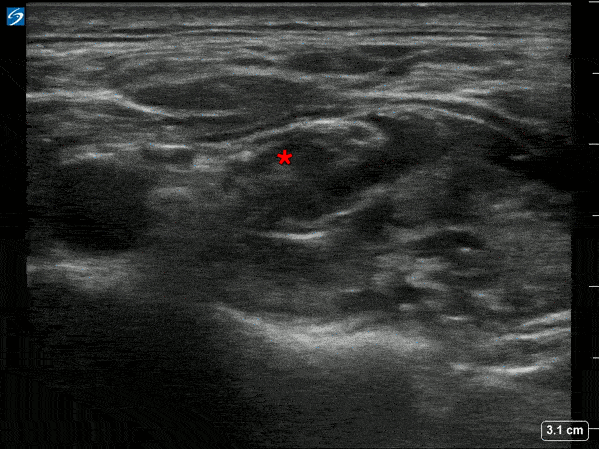

In plane supraclavicular nerve block used for pain management in a patient with a mid shaft humerus fracture. Spread of anesthetic can be seen around the brachial plexus bundle (*). Michael Macias